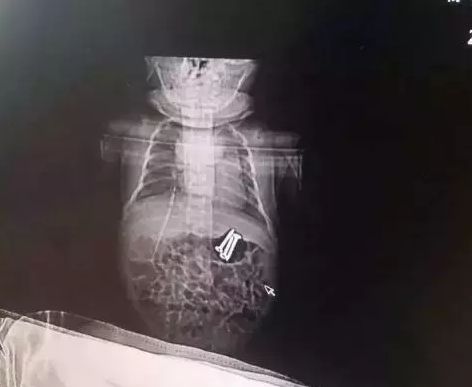

听见乐乐的话,惊慌失措的楠楠立马带着二宝去了当地医院就诊。在医院给二宝拍片儿后,发现二宝胃中不仅有螺丝钉,而且还有3枚。